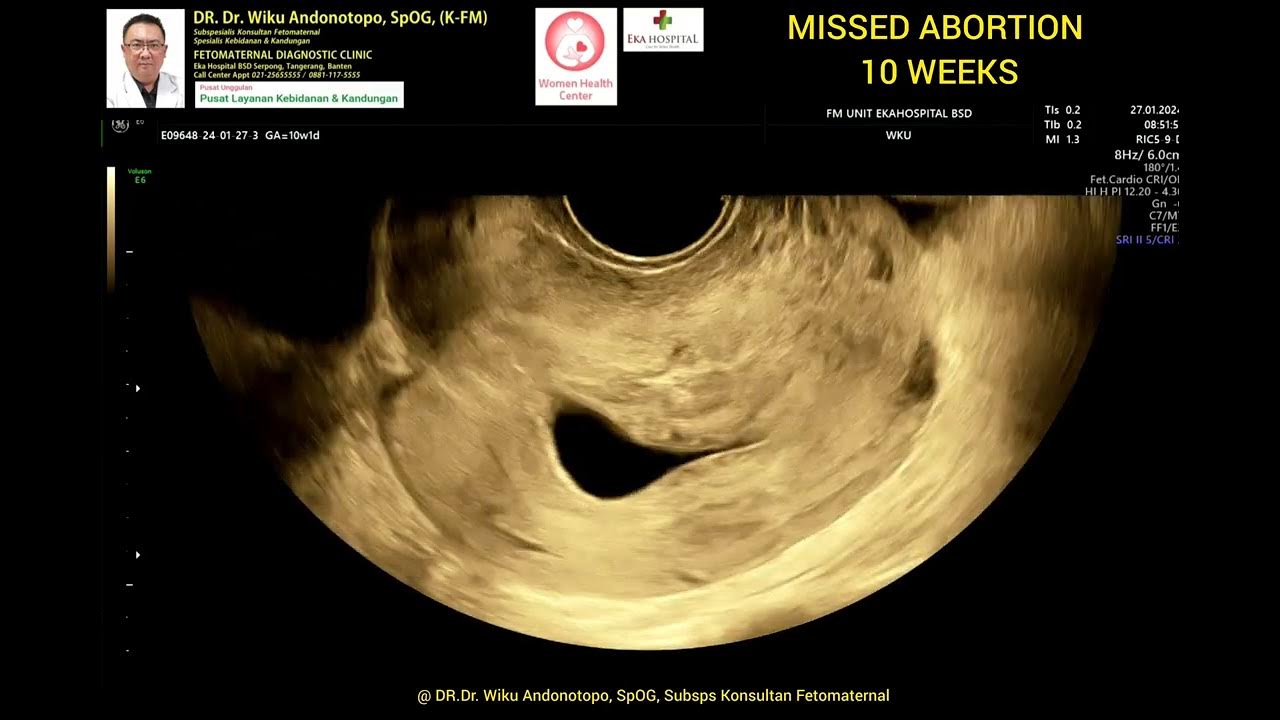

Bei einer Missed Abortion fehlen Symptome wie Schmerzen, Blutungen und Krämpfe Von einem verhaltenen Abort - in der Fachsprache "missed abortion" genannt - spricht man, wenn der Embryo oder Fetus stirbt und unbemerkt zusammen mit der Plazenta in der Gebärmutter verbleibt und nicht durch eine Blutung ausgestossen wird

Häufig bemerkt auch die Schwangere die verhaltene Fehlgeburt nicht. In einem unteren Beitrag einer anderen Betroffenen schreiben Sie, dass Fehler bei der Zellteilung vermutlich früher Abgänge veursachen, nicht erst in SSW 10 Ich hatte eine Ausscharbung nach Missed Abortion am 01.10 letzten Jahres

Supporting Women Through The Experience Of Missed Abortion MedShun. Häufig bemerkt auch die Schwangere die verhaltene Fehlgeburt nicht. Der Embryo ist aber gewachsen und sie sprach von Windei und man sieht keine embryonale Struktur